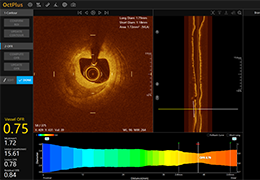

Designed for surgeons, Pro Surgical 3D makes it easy to view patient scans quickly. Pro Surgical 3D facilitates the optimal 3D treatment and assessment workflows based on X-ray CT and MRI scans – and best of all, it’s FREE!

High-quality and fast 3D reconstruction and 3D rendering

Performs 3D reconstruction and volume rendering.